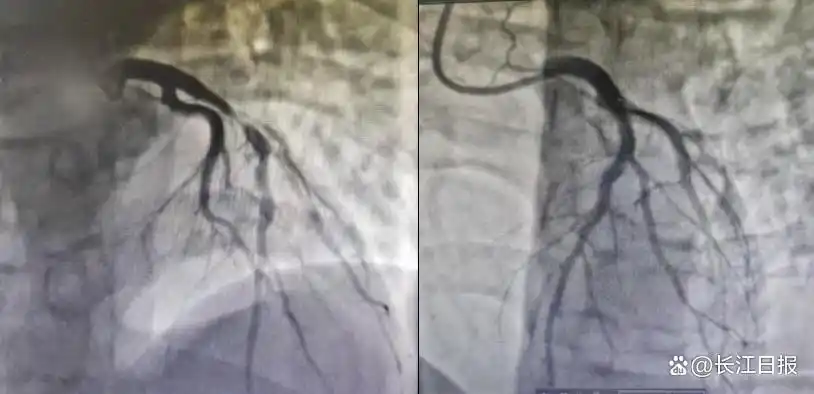

• 小伙熬夜+酗酒引發(fā)心梗,不良生活習慣正在摧毀年輕人的心臟

小伙熬夜+酗酒引發(fā)心梗,不良生活習慣正在摧毀年輕人的心臟

“以為年輕扛得住,沒想到死神離得這么近。”在武漢科技大學附屬天佑醫(yī)院CCU(心臟重癥監(jiān)護室)病房里,劫后余生的22歲青年彭某(化姓)仍心有余悸。一場因長期熬夜